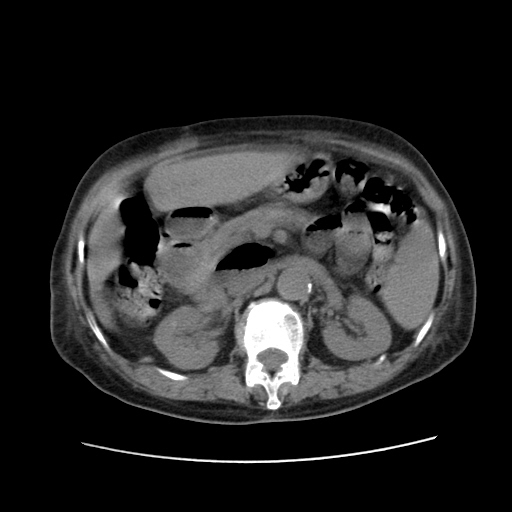

女,77.无不适

肝脏变异、异位胆囊,肝右叶肝内胆管结石并肝内胆管扩张。

肝右叶肝内胆管结石并肝内胆管扩张。

肝右叶肝内胆管结石并肝内胆管扩张

胆总管扩张

肝右叶肝内胆管结石并肝内胆管扩张。另:慢性胆囊炎!胆囊窝积液!

肝右叶肝内胆管结石并肝内胆管扩张。胆总管下段梗阻,考虑壶腹部占位。

右侧肝内胆管局限性扩张,其内密度不均匀,扩张的胆管壁增厚,考虑肝内胆管炎合并结石可能性大

肝右叶肝内胆管结石并肝内胆管扩张。胆总管下段梗阻,考虑壶腹部占位。支持